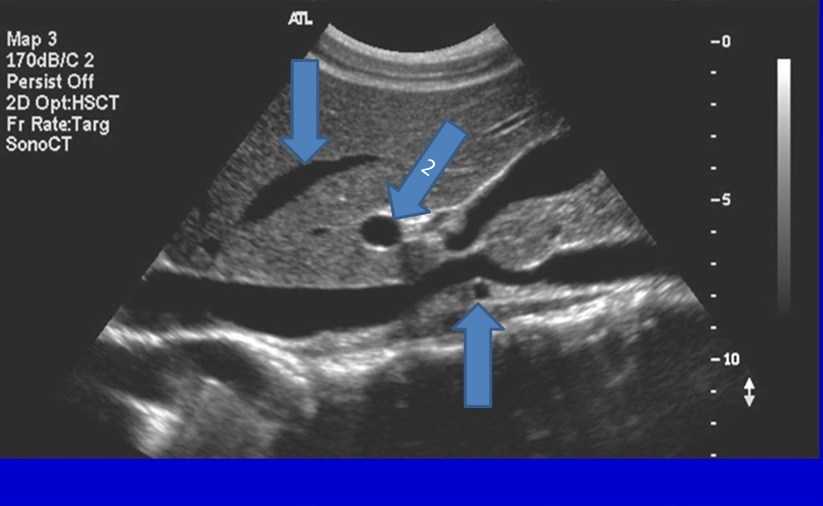

Q

From the left to right label the structures

A

1. IVC

2. Aorta

3. Left Renal Artery